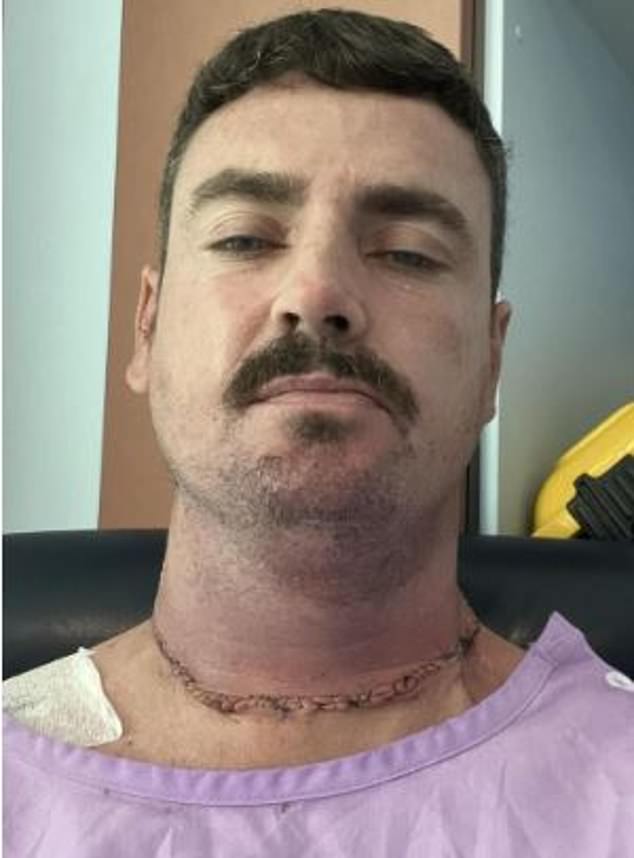

The patient Nicholas Smithson says his hairdresser first noticed the mole across his neck and by that time, he alerted him that something was not right. But it was just too late as that suspicious mark was actually cancer and now, he’s been given just a few months to live.

“I had no clue about this. I went to the doctors at the start and told them about the mole and they reassured me that it was nothing to worry about. And then when I went back again, I was offered the most haunting news ever”- Nicholas explained.

Still not happy with their diagnosis, he went to a skin specialist who was very alarmed by the presence of the mole. He immediately took a biopsy and informed him that it was cancer and had already spread.

After having the mole removed and the lymph nodes associated with it, he noticed another growth behind his ear and it was clear that there was no end. The tumor was spreading.